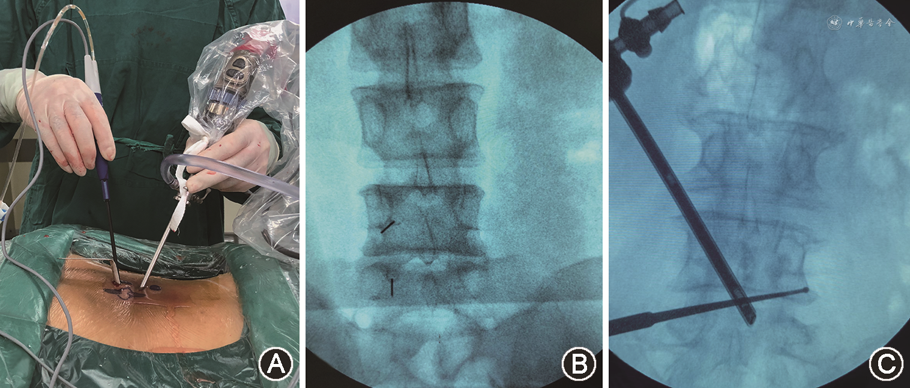

1.UBE组:患者全身麻醉俯卧位,通过C型臂透视定位,入路选择:根据患者是否伴有椎间孔狭窄选择,如伴有一侧椎间孔狭窄,则选择椎间孔狭窄对侧入路;如不伴有椎间孔狭窄则选择症状较重侧或根据医生习惯选择。切口设计:(1)左侧操作:后正中线旁开5 mm,下方切口位于下位椎板头端水平,上方切口以下方切口上移2.5~3.0 cm(根据患者脂肪厚度)为准;(2)右侧操作:后正中线旁开10 mm(右手为工作通道),切口水平位置较左侧略向尾侧移。观察通道的切口4~6 mm,工作通道的切口8~10 mm。逐级套筒抵至上位棘突椎板交界处尾侧,工作通道深筋膜做“十”字切开,逐级套筒扩张后,置入观察通道与工作通道。清理软组织后,在多裂肌三角内创建“初始营地”,依次切除上位椎板下缘、下关节突内缘、上关节突内缘及下位椎板上缘,游离黄韧带止点,暴露神经根的肩部及腋部,行同侧侧隐窝减压。减压满意后,沿黄韧带深层表面行对侧过顶减压,磨除对侧椎板腹侧及下关节突腹侧的骨质(3~4 mm),切除部分对侧下关节突腹侧面,暴露上关节突内侧缘,行对侧侧隐窝减压。若需行椎间孔减压,向头侧移动,切除上关节突尖部及椎间孔区黄韧带,充分暴露出行根并探查。减压满意后再次探查全椎管,确认减压满意后充分止血,内镜监视下置入引流管,固定。消毒,缝合切口,无菌敷料包扎后术毕(图1、2)。

UBE组患者术后严格腰围固定卧床1 d,PILF组患者严格腰围固定卧床2~3 d,对症治疗;根据术后引流量情况拔出引流管,并记录每日术区引流量,计算术后总引流量。两组患者均于拔管后复查数字化X线及CT,术后6个月内复查MRI。